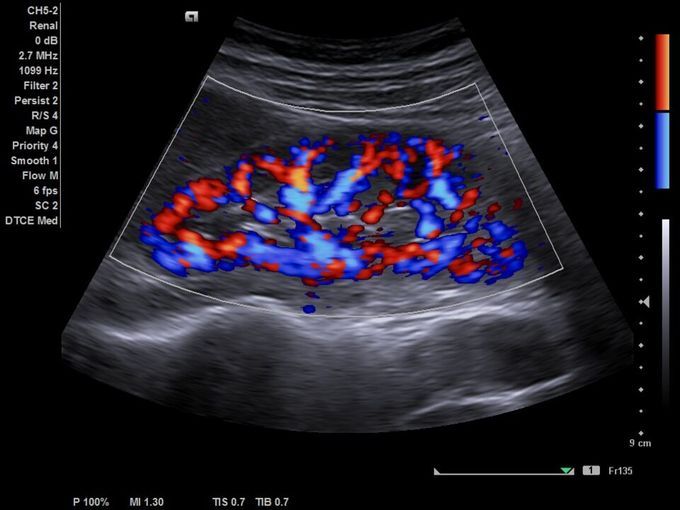

Кроме новой техники, можно заказать восстановленные медицинские системы: ультразвуковые сканеры, томографы, флюороскопы, ангиографы и хирургические установки С-дуга.